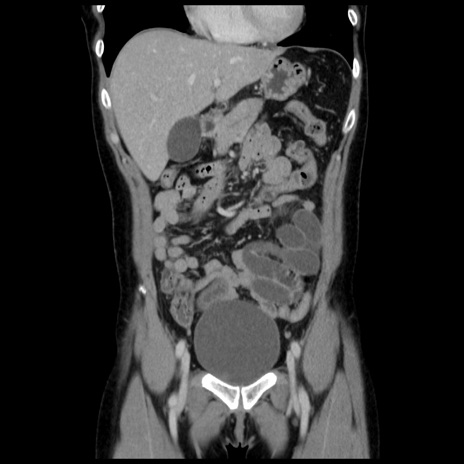

症例10(冠状断像)

【症例】 50歳代女性

【主訴】 腹痛

【現病歴】前日生レバーを食べた。今朝に排便あり。 昼前に突然発症の腹痛を生じ、当院救急外来を受診した。

【既往歴】 子宮筋腫にてで子宮全摘後

【身体所見】 意識清明、腹部:平坦、軟、下腹部やや左を中心に圧痛・反跳痛あり、筋性防御あり

【データ】WBC 7800、CRP 0.07